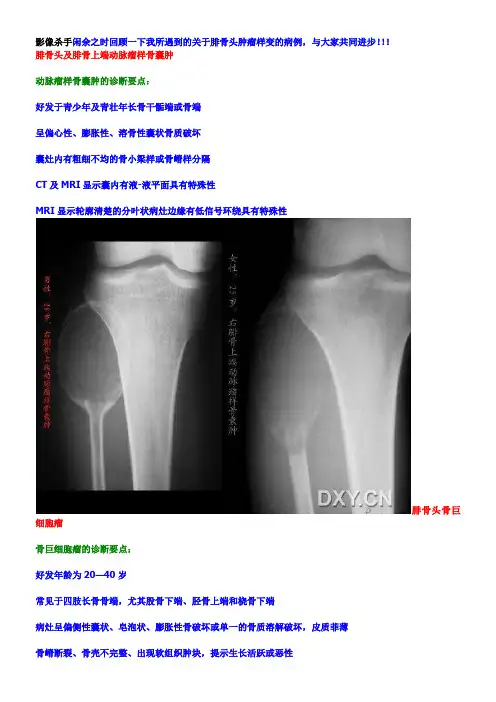

影像杀手闲余之时回顾一下我所遇到的关于腓骨头肿瘤样变的病例,与大家共同进步!!!腓骨头及腓骨上端动脉瘤样骨囊肿动脉瘤样骨囊肿的诊断要点:好发于青少年及青壮年长骨干骺端或骨端呈偏心性、膨胀性、溶骨性囊状骨质破坏囊灶内有粗细不均的骨小梁样或骨嵴样分隔CT及MRI显示囊内有液-液平面具有特殊性MRI显示轮廓清楚的分叶状病灶边缘有低信号环绕具有特殊性腓骨头骨巨细胞瘤骨巨细胞瘤的诊断要点:好发年龄为20—40岁常见于四肢长骨骨端,尤其股骨下端、胫骨上端和桡骨下端病灶呈偏侧性囊状、皂泡状、膨胀性骨破坏或单一的骨质溶解破坏,皮质菲薄骨嵴断裂、骨壳不完整、出现软组织肿块,提示生长活跃或恶性局部切除易复发、恶变!左腓骨头骨巨细胞术后复发恶变为恶性骨巨细胞瘤右腓骨上端骨瘤(疏松型)【该部位出现骨瘤罕见,但是病理结果是骨瘤(疏松型)真是】骨瘤是一种成骨性良性肿瘤,占骨良性肿瘤的8%。